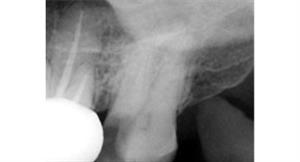

Root Canal Treatment

Before